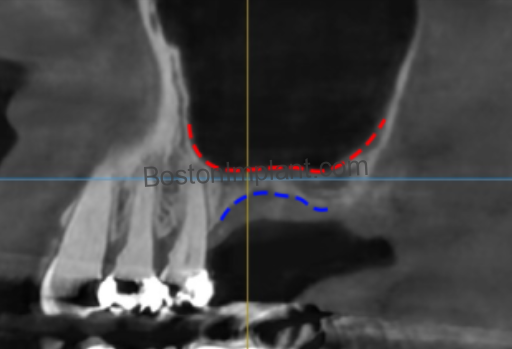

• The Risk: This occurs in roughly 20% to 25% of cases. It is more common in patients with a “thin” membrane phenotype or those with internal bony walls called septa.

• Prevention & Clinical Protocol: Recent research shows a strong correlation between gum tissue thickness and membrane thickness. Dr. Lee utilizes high-resolution 3D CBCT imaging to map your specific anatomy before surgery. This allows for a customized approach that respects these delicate boundaries.

The lateral wall of the sinus contains small blood vessels that must be navigated carefully during the creation of the surgical window.

• The Risk: Approximately 10% of patients have larger vessels in this area that could cause significant bleeding if not identified during planning.

• Prevention & Clinical Protocol: Through “Vessel Mapping” via 3D CBCT imaging, Dr. Lee identifies the exact location of these vessels and plans the surgical access to bypass them entirely.